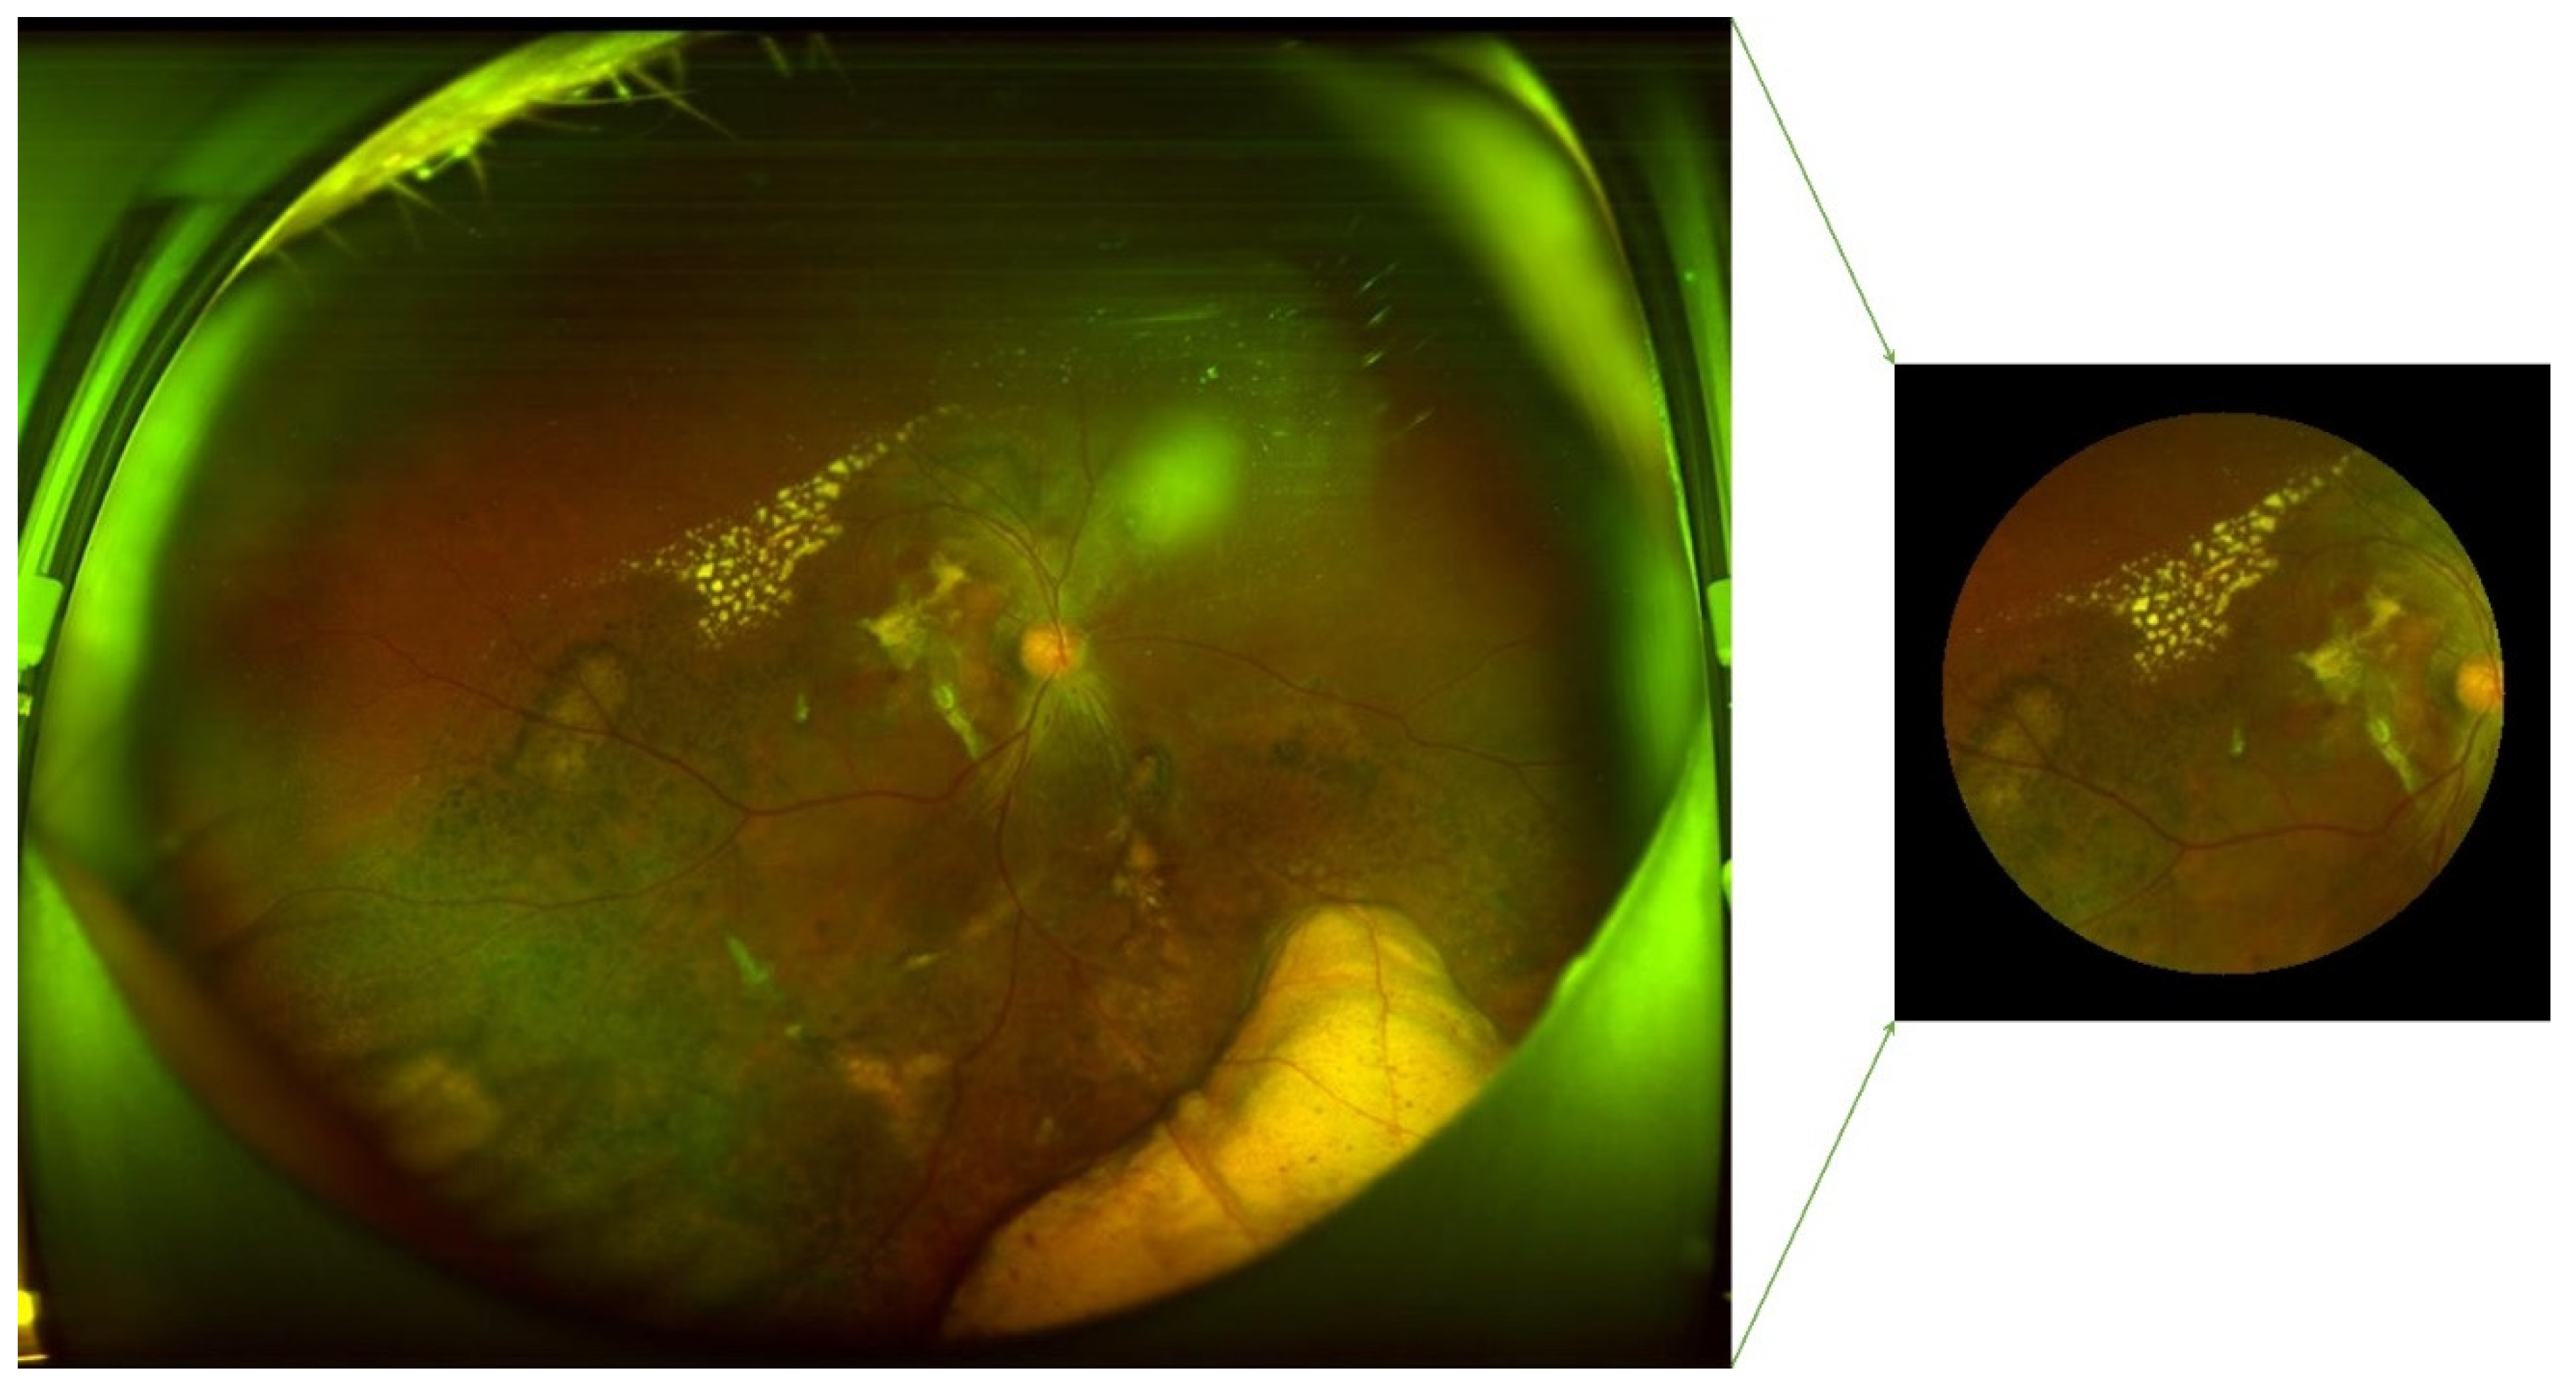

445 AMD and 2874 normal regular CFP original images are collected from open sources. Examples of AMD (A, B, and C) and normal (D, E, and F) are illustrated in

Figure 3. The drusen are clearly illustrated in A and B, and symptoms of hemorrhagic spots, vitreous debris, and subretinal hemorrhage with residue in the perimacular region are presented in subfigure A. Subfigure C shows symptoms of large choroidal vessels and deep capillary plexus vessel in the macular region and glial scar tissue in the perimacular area. Preprocessing of rotating and SPN noise-adding are performed on the AMD regular CFP images.

Figure 3.

Original figures of regular CFP images. Subfigures of D, E, and F are related to normal subjects. Subfigures of A and C are related to the wet-AMD subjects in the late stage, A is with symptoms of serous RPE detachments caused by the fluid exuded from the subretinal neovascular. C is with symptoms of sub-foveal hemorrhage with RPE detachment. B is with symptoms of late dry AMD of PRD detachments with large scale of fused drusen accompanied by hyperpigmentation.